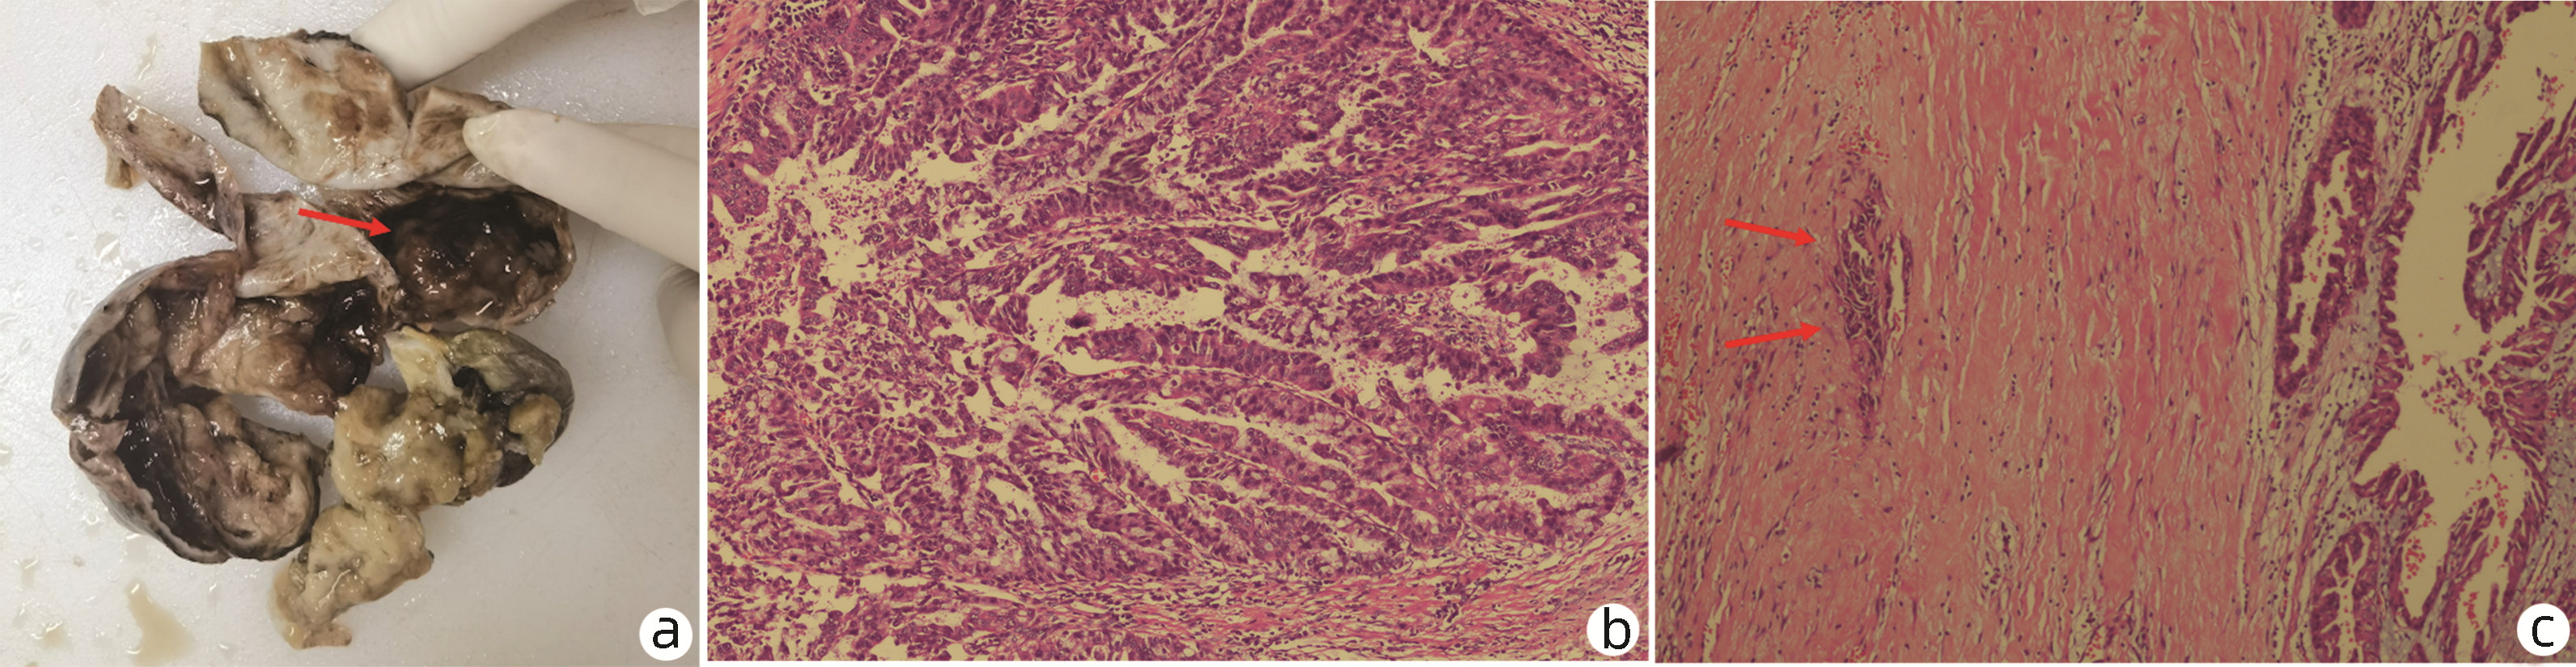

A case of chronic gelatinous ascites caused by giant intraductal papillary mucinous neoplasm of the bile tract

Congying CHEN, Ruling ZHANG, Liang QIAO, Lungen LU, Hui ZHOU

2023, 39(1): 147-151. DOI: 10.3969/j.issn.1001-5256.2023.01.022

Abstract(2426) HTML (1406) PDF (2992KB)(126)

Abstract: